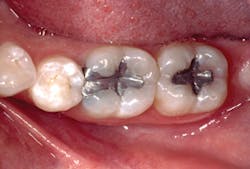

When all of these technologies are added into a posterior composite protocol, it allows the dental team to place excellent restorations in 30% to 60% less time (Figs. 3 and 4).